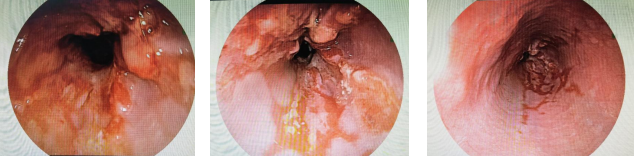

最终,在国产自拍av 消化内镜中心进行了无痛舒适化高清胃镜检查后,张先生被确诊为食管中低分化腺癌。

“食管癌早期症状与反流性食管炎有许多相似性,都可能出现胸骨后反酸、烧心等不适,容易导致误诊、漏诊。大家切不可对胃食管反流病掉以轻心,别把反流不当回事,即使已经胃镜确诊胃食管反流病,也要定期复查胃镜。”

缪晓峰副主任医师提醒,食管恶性肿瘤病理多以鳞癌为主,而食管腺癌相对少见,其好发部位多位于食管下段(靠近胃贲门),常与胃食管反流病及巴雷特食管相关。

如果反流性食管炎久治不愈,一定要引起重视,胃镜检查不可缺少,必要时还要做精查放大胃镜。